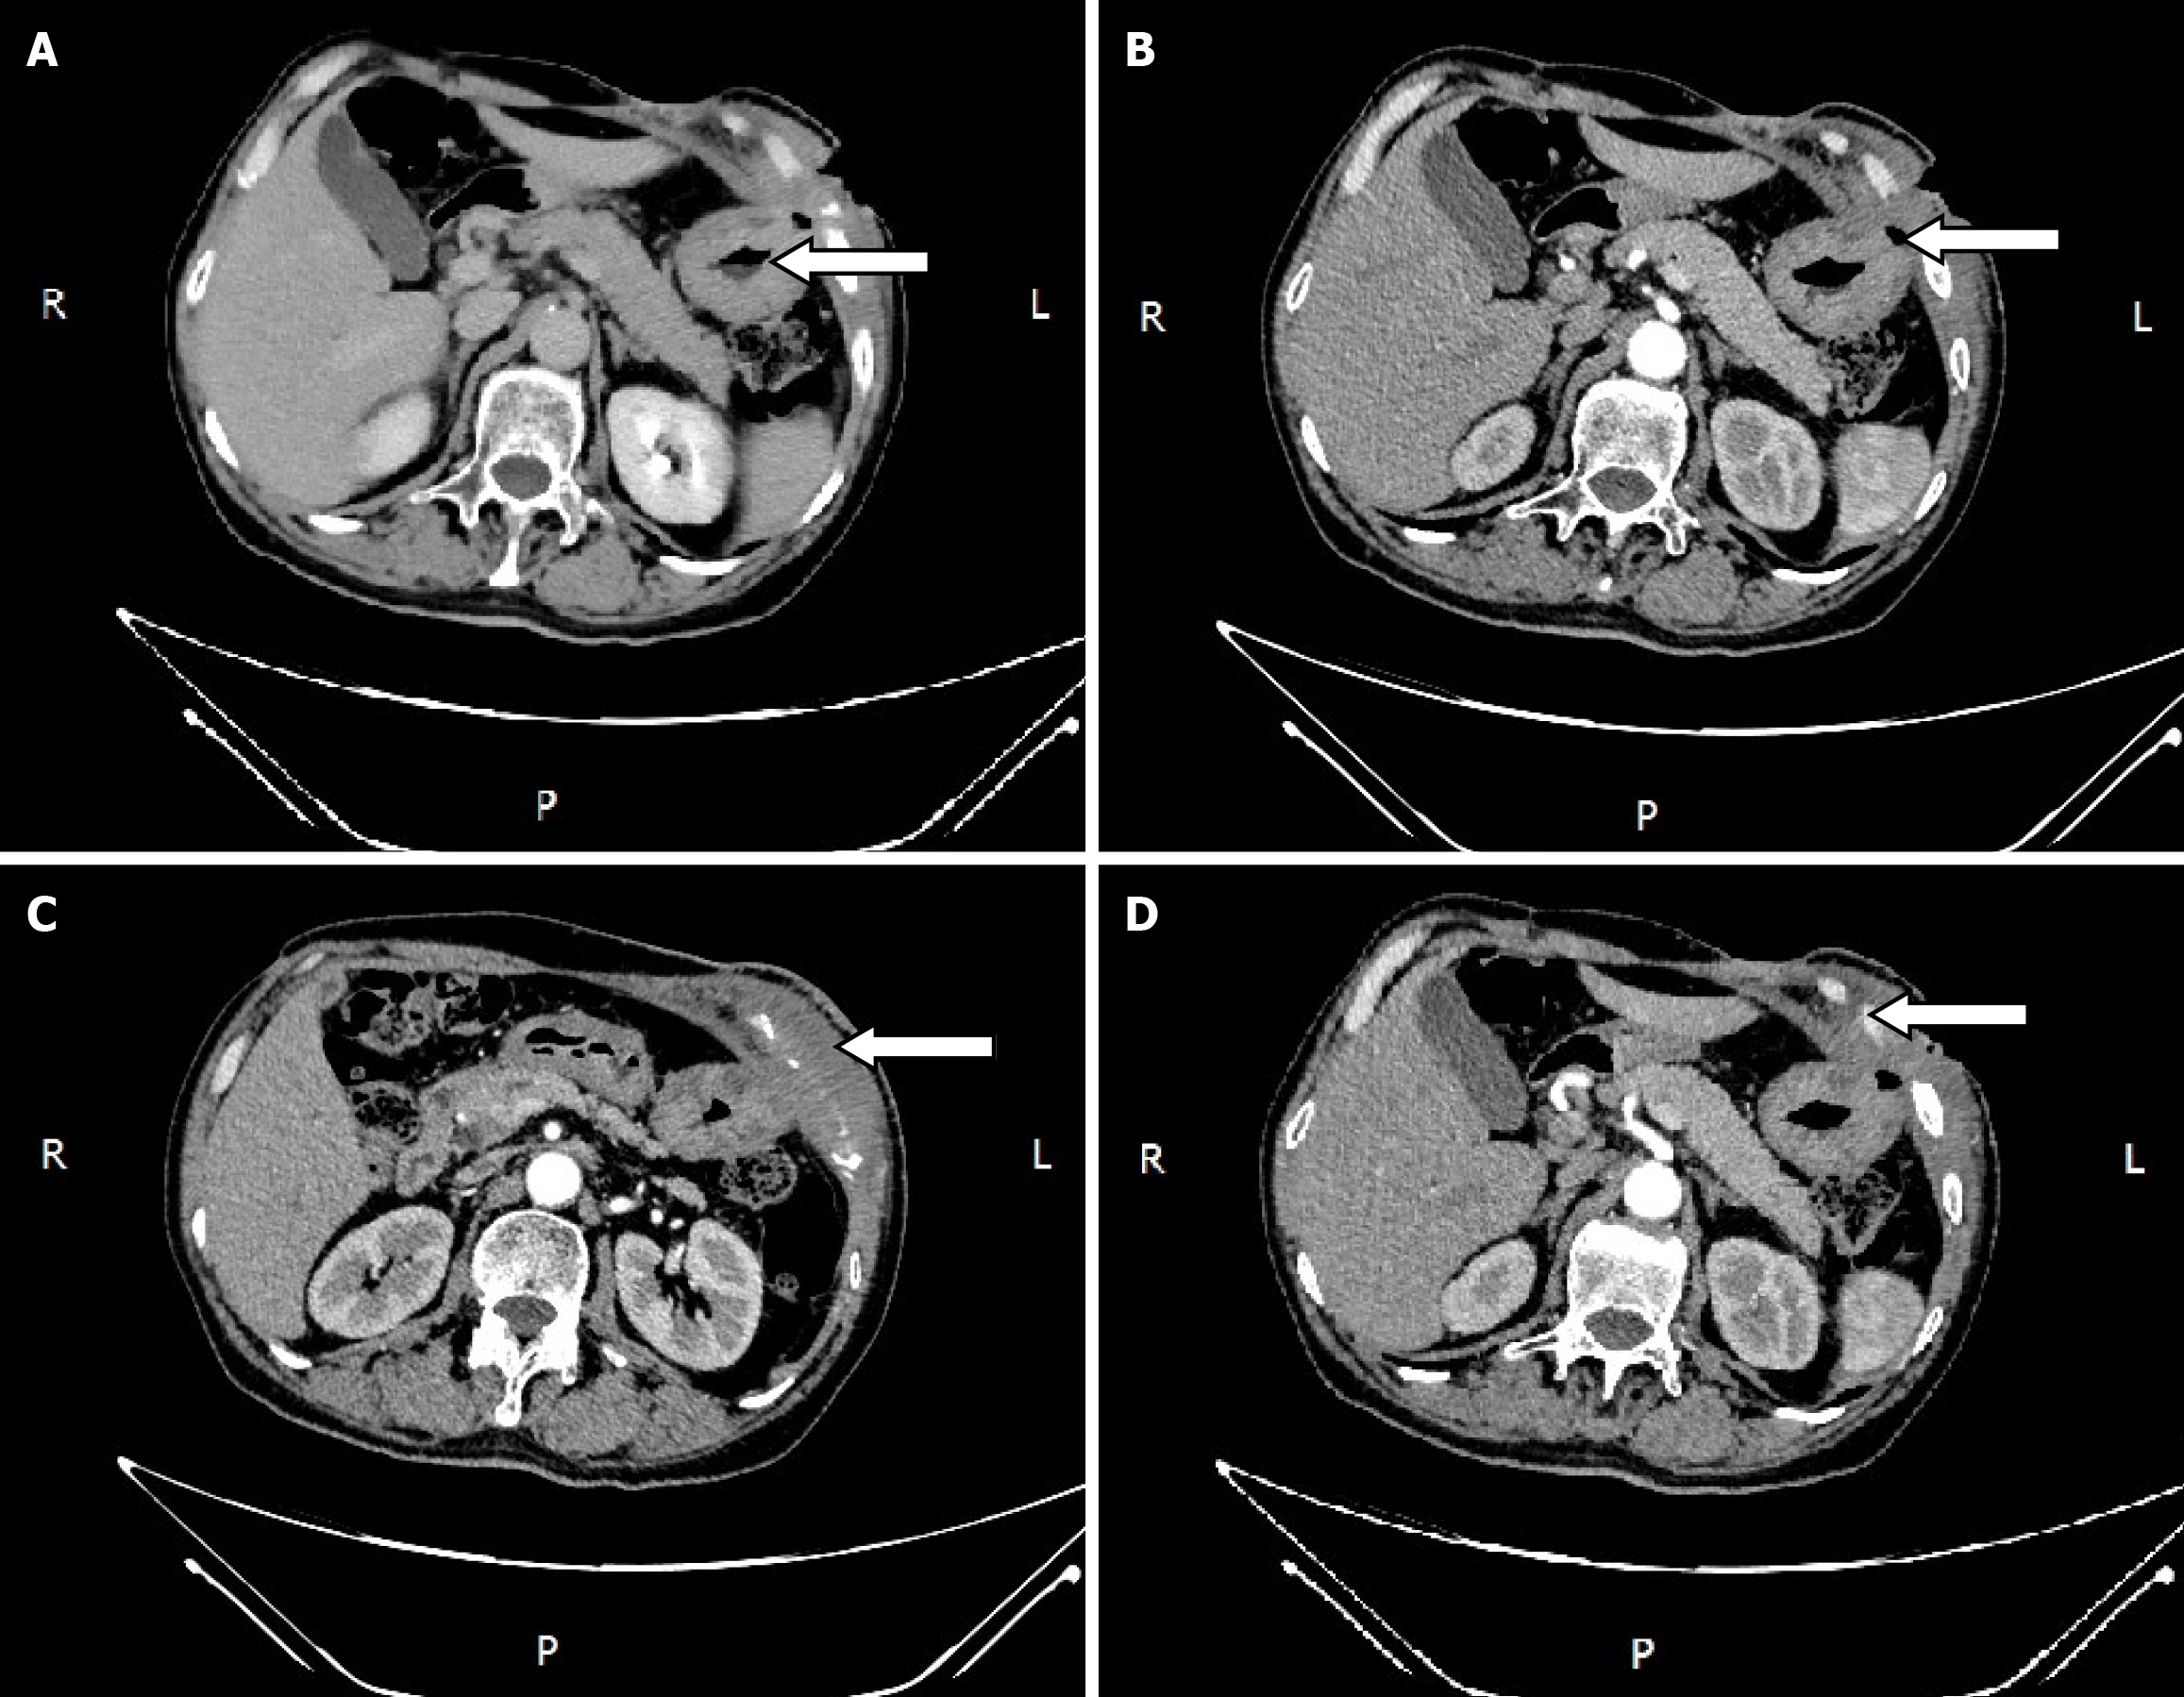

During the postoperative fasting period, we consulted with a nutritionist again. The energy and nitrogen sources were supplied according to the patient's disease status until he returned to a roughly normal diet and then changed to oral enteral nutrition. Drainage tubes of smaller diameter were placed successively and then removed. Reexamination by abdominal CT confirmed that the thoracoabdominal wall swelling had improved (Figure 5), gastric endoscopy verified gastric ulcer improvement and the gastric fistula was not observed at this time (Figure 6). The patient’s clinical symptoms, especially pain, were alleviated. Pathological examination of the sinus showed fibrous and inflammatory granulation tissue with a giant cell reaction. His condition improved and he was again discharged on June 17, 2020.

On July 21, 2020, the patient was again hospitalized due to the unsatisfactory outcome of more than one month of outpatient treatment. The abdominal wall fistula and incision on the adjacent left chest wall had not completely healed. The patient and his family eventually agreed to an exploratory laparotomy. As the rib CT scan displayed destruction of the left 7th, 8th and 9th anterior ribs and costal cartilage, we consulted with thoracic surgeons and determined that rib surgery could be performed right after exploratory laparotomy.